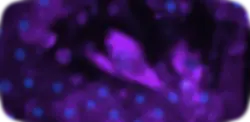

ER Stress

BIP/GRP78 Expression

Hoechst (Nuclei) BIP/GRP78 (ER Stress)